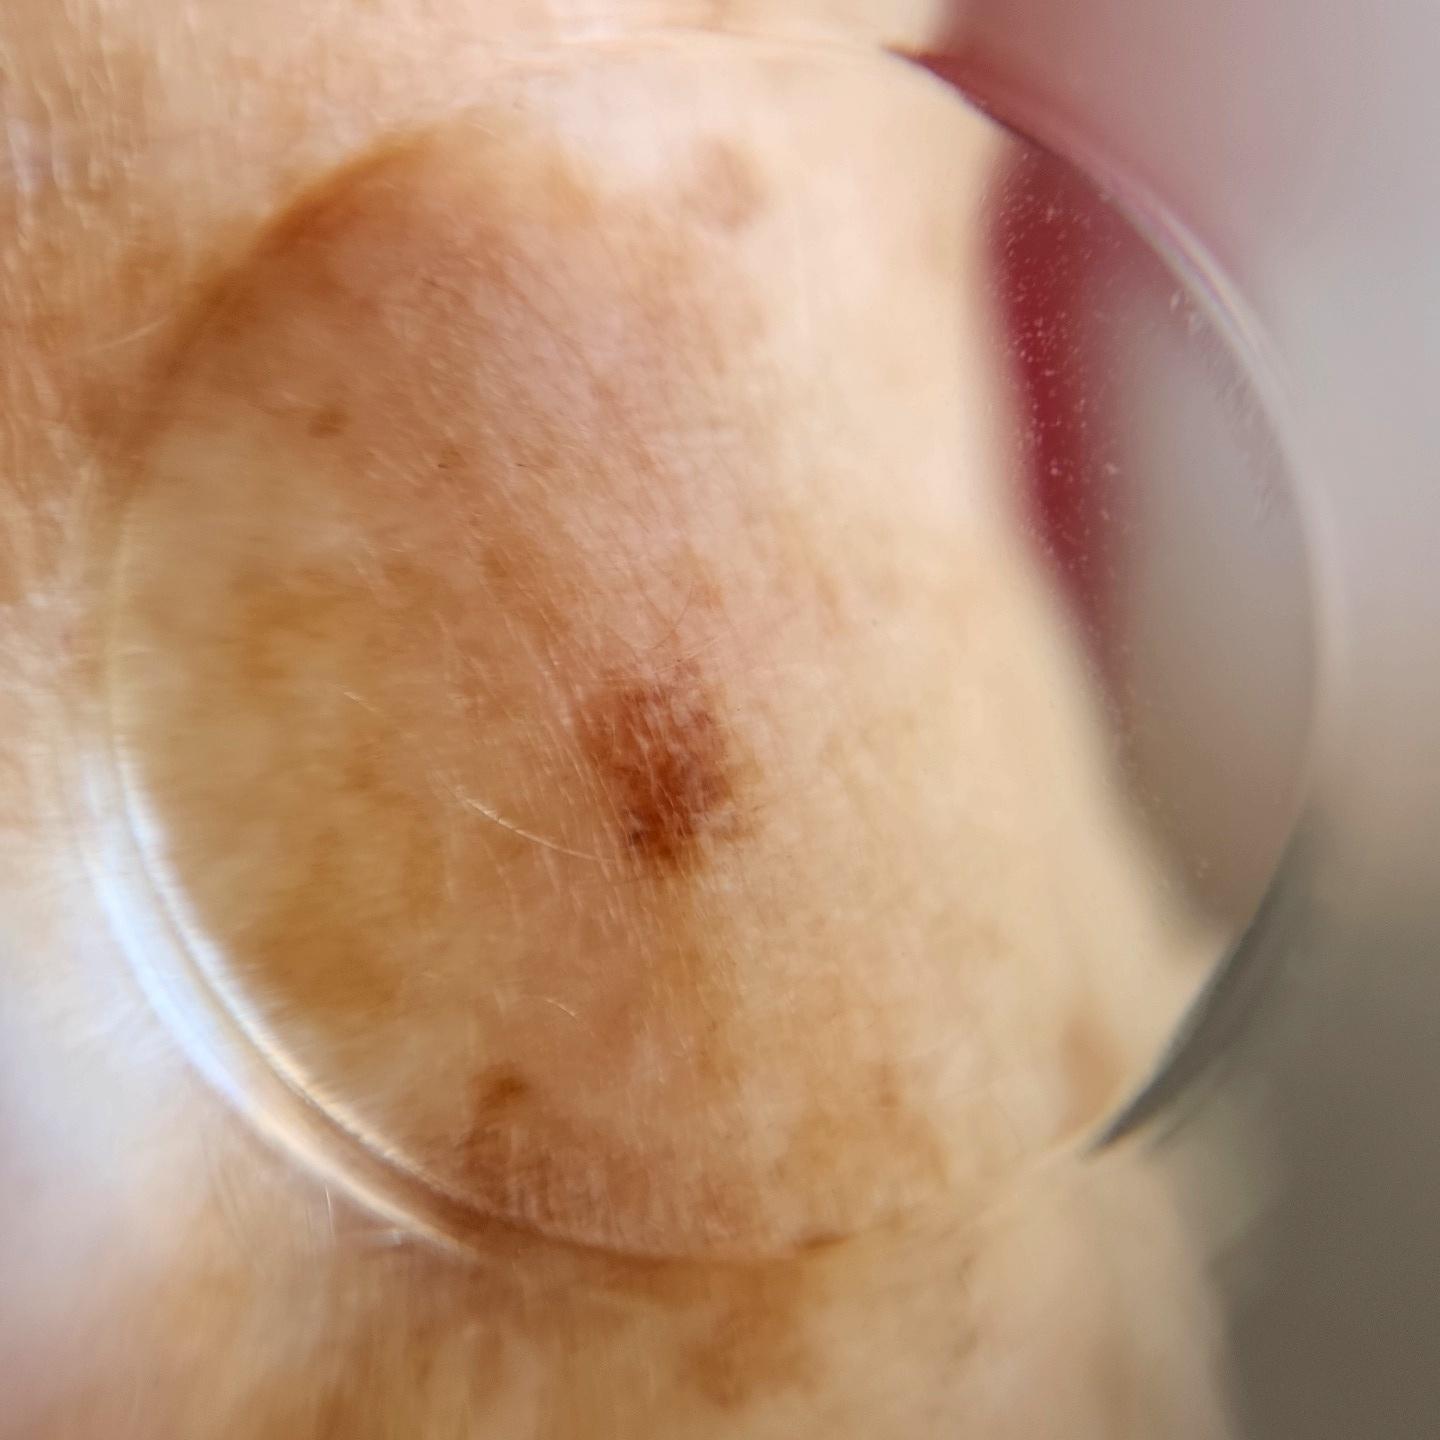

ISIC_4949599

Clinical

Field Value

diagnosis_1 Benign

image_type dermoscopic